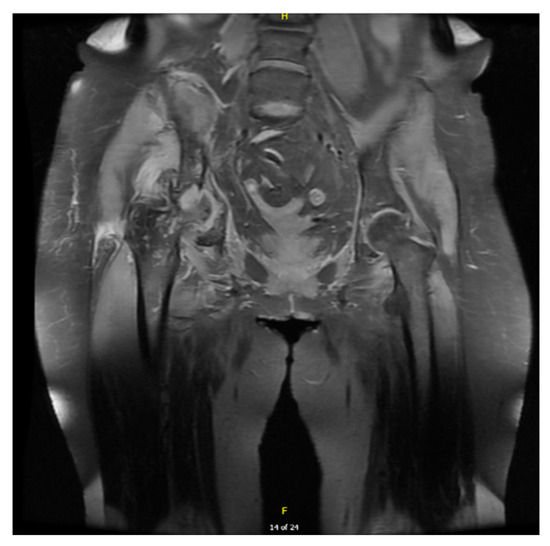

2. Case Presentation